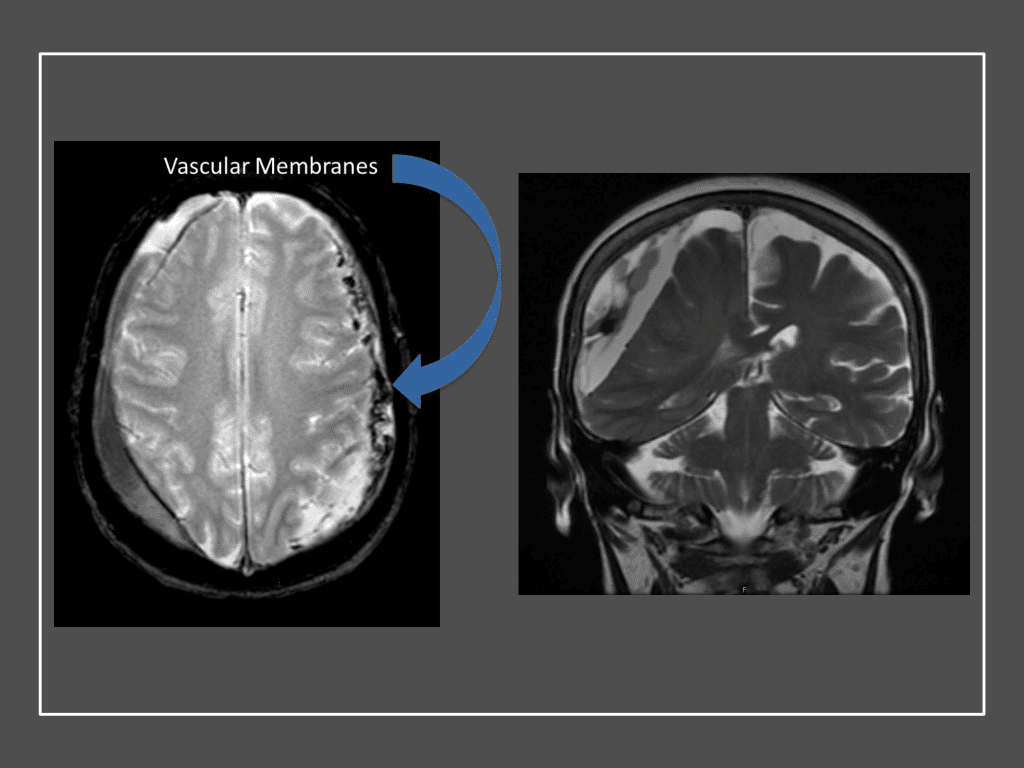

Although conventional surgical methods, such as burr hole irrigation or observation in asymptomatic or minimally symptomatic patients have been the mainstay of treatment, middle meningeal artery (MMA) embolization has emerged as a promising adjunctive or alternative treatment. MMA embolization is a neuroendovascular technique which involves placing a microcatheter into the Middle Meningeal Artery, most commonly on the side of the cSDH (occasionally, bilateral embolization has been recommended for larger or bilateral collection. Embolization of both the anterior (frontal) and posterior (parietal) division is performed using a variety of embolic materials (liquid NBCA, Onyx, coils), although polyvinyl alcohol particles of <250 microns are most commonly used to achieve distal penetration and occlusion of the pre-capillary and capillary beds. The micro-leakage of blood and transudative proteinaceous inflammatory fluid in these inflammatory membranes is creating an imbalance in cycle of resorption and preventing resolution or promoting recurrence or growth of these cSDH collections and associated mass effect and midline shift.

Figure 7. Neovascularized membranes within cSDH